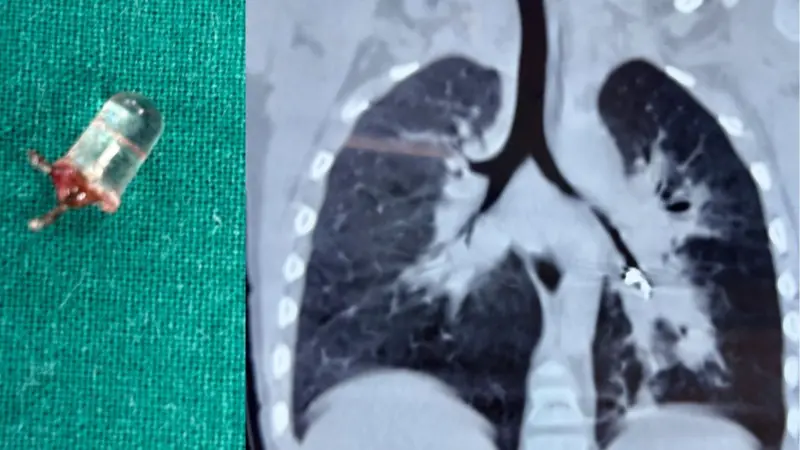

ڈاکٹروں نے تین سالہ بچے کے پھیپھڑے میں پھنسے دھاتی ایل ای ڈی بلب کو کامیاب آپریشن کی مدد سے نکال دیا۔

ڈاکٹرز کو راہل کے پھیپھڑوں سے ایل ای ڈی بلب نکالنے کے لیے اُن کے جسم پر چار سینٹی میٹر کا کٹ لگانا پڑا۔ ڈاکٹروں نے کھلونا کار کا ایل ای ڈی بلب نکالنے کا کامیاب آپریشن کیا جس کے بعد بچے کے پھیپھڑوں نے مکمل کام کرنا شروع کیا۔

اس آپریشن میں حصہ لینے والے سرجن ڈاکٹر ویمیش راجپوت نے کہا کہ ’یہ بہت ہی نایاب کیس تھا جس سے ہم نے ڈیل کیا۔ چھوٹا ایل ای ڈی بلب پھیپھڑوں میں گہرائی تک چلا گیا تھا اور اسے نکالنے کی ابتدائی کوششیں ناکام رہیں تھیں۔تاہم ’منی تھوریکوٹومی‘ (سرجری کا ایک طریقہ کار) کے ذریعے ہم نے بچے کا کامیاب آپریشن کیا اور ایل ای ڈی بلب نکال لیا گیا۔‘